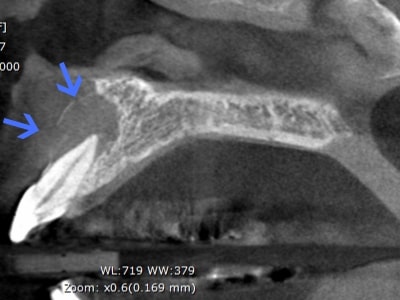

症例2歯性上顎洞炎(副鼻腔炎)

Before

歯性上顎洞炎(副鼻腔炎)

根尖病巣により洞底膜がラッパ状に開いている。

After

6ヶ月後のCT

洞底膜はきれいに再生され病巣は消失しております。